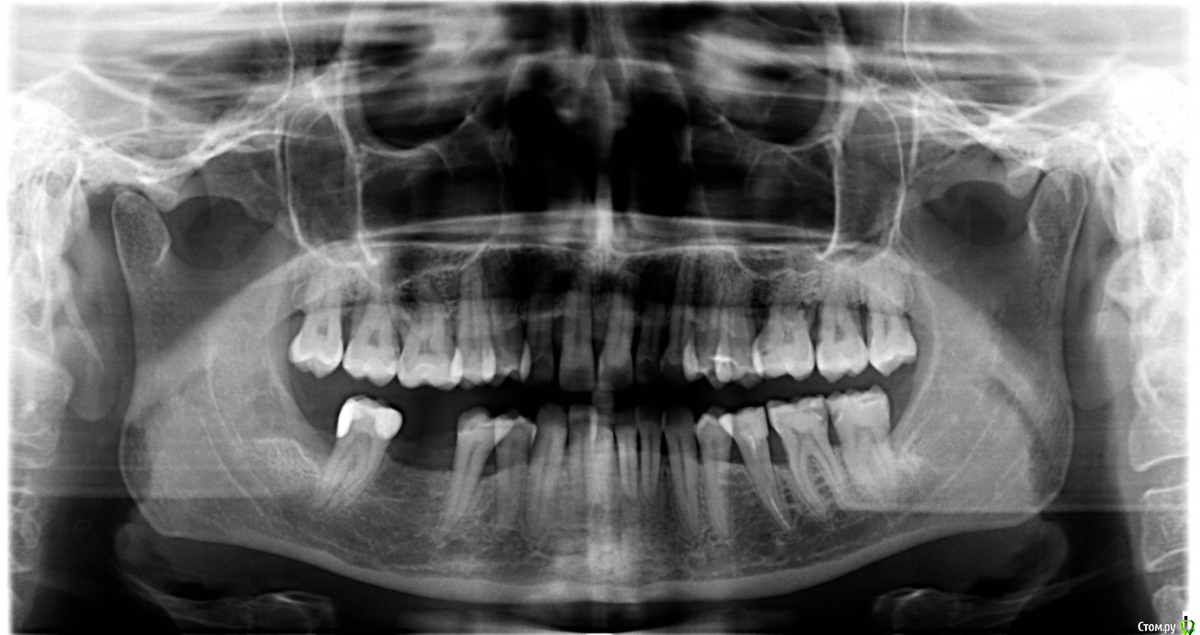

Opdihatop Опубликовано 9 мая, 2016 Поделиться Опубликовано 9 мая, 2016 (изменено) Здравствуйте, коллеги! Хотел бы представить вашему вниманию вот такой вот случай и спросить совета. В принципе, по окклюзии ничего особенного по лечению нет, но вот проблемы с пародонтом (на КТ по кости все заметно хуже, чем на орто), делают невозможным все, продуманные мной варианты. Может у кого-то было что-то подобное? Может поделитесь советом, а то помочь человеку надо, а я в тупике. Буду заранее очень благодарен за помощь! Изменено 9 мая, 2016 пользователем Opdihatop Ссылка на комментарий

Opdihatop Опубликовано 13 мая, 2016 Автор Поделиться Опубликовано 13 мая, 2016 чтобы вывести в первый класс, для этого надо челюсть поставить в первый класс. (проблема не в положении зубов, а положении челюсти), что вам мешает это сделать? Да нет, тут как раз проблема в зубах, так как из-за вторичной адентии 13 зуба фронт верха уехал вправо, да и правый боковой сегмент немного мезиализировался. Как тут поможет постановка челюсти в первый класс? Даже если бы вышеупомянутой проблемы по зубам не было бы, то для постановки челюсти эластиков скорее всего не хватило бы, а корректоры второго класса с таким пародонтом я ставить не рискнул бы.Вот в связи с этим и возник вопрос по первому классу, так как дистализировать не получится и удалять нельзя, потому что с таким пародонтом промежутки не закроются... Ссылка на комментарий

Yana guapa Опубликовано 13 мая, 2016 Поделиться Опубликовано 13 мая, 2016 Да нет, тут как раз проблема в зубах, так как из-за вторичной адентии 13 зуба фронт верха уехал вправо, да и правый боковой сегмент немного мезиализировался. Как тут поможет постановка челюсти в первый класс? Даже если бы вышеупомянутой проблемы по зубам не было бы, то для постановки челюсти эластиков скорее всего не хватило бы, а корректоры второго класса с таким пародонтом я ставить не рискнул бы.Вот в связи с этим и возник вопрос по первому классу, так как дистализировать не получится и удалять нельзя, потому что с таким пародонтом промежутки не закроются... Здесь чистый второй класс. Расчет ТРГ и индекс APDI Вам ясно это дают понять. конечно об эластиках речь не идет (я из вообще не применяю, только корректоры). Но не всегда первый класс - панацея. Зависит от того, какую вообще цель преследуете. Иногда можно оставить в привычном втором классе и со спокойной совестью отпустить)))))) Ссылка на комментарий

Opdihatop Опубликовано 13 мая, 2016 Автор Поделиться Опубликовано 13 мая, 2016 (изменено) Попова послушать лично не смогу. Я живу в Украине и он к нам, по понятным причинам, не приезжает (был когда-то на конгрессе, но там лекция по минивинтам была). 1) По ТРГ про второй класс я с Вами абсолютно согласен. Здесь главное, что волнует пациентку, это создание места под 13 зуб. Да, она согласна корректировать все остальные проблемы, но не пойдет на лечение, если "ее" цель не будет достигнута. И да, я понимаю, что идеала тут достичь у меня не получится.2) Так уж сложилось, что кросс-эластиками я не так уж много работал, как то пациенты не подворачивались. По-этому позвольте в связи с этим вопрос: а не навредит ли нам тут вестибулярный наклон верхних моляров, который несомненно возникнет за счет тяги (они наклонены орально незначительно)? Да, я понимаю, что и нижние наклонятся орально, но все же.3) Почему Вы против, пусть даже не сарпе, так хоть послабления небного шва в этом случае? С трудом верится, что в этом возрасте, пусть даже на самолигах, получится получить стабильное расширение.И последнее 4) Я встречал в литературе успешное применение, при подобном пародонте, дистализации на в/ч при непрямом анкораже на м/и. Подобное лечение (с нормальной костью) неоднократно производил и успешно. Как Вы считаете, рискнуть или успех маловероятен? Простите за сумбур, просто много мыслей в голове. Изменено 13 мая, 2016 пользователем Opdihatop Ссылка на комментарий